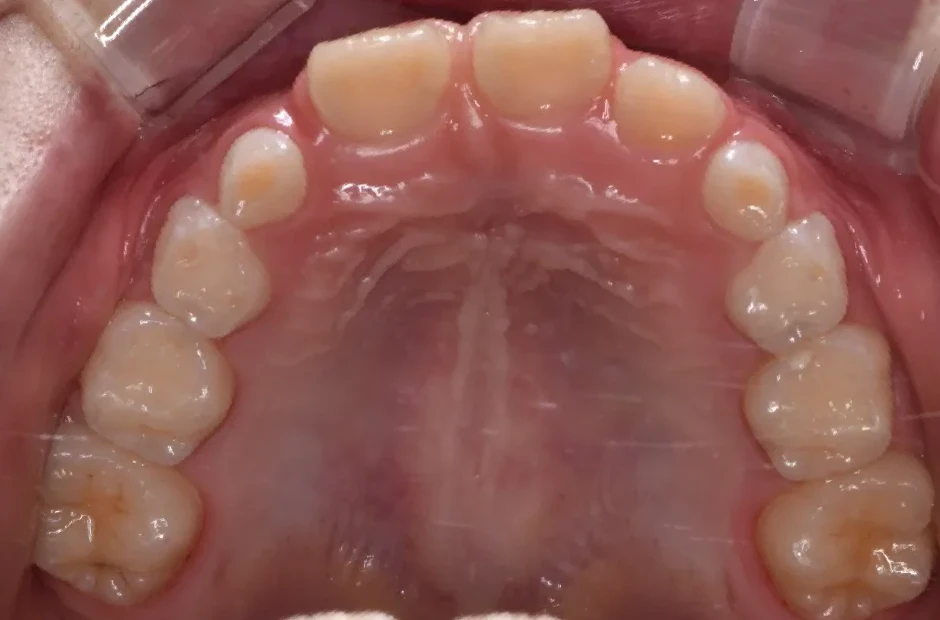

出っ歯

| 診断名・主訴 | 出っ歯 |

|---|---|

| 年齢・性別 | 16歳・男性 |

| 治療期間・回数 | 1年4か月 |

| 治療に用いた主な装置 | ブラケット |

| 抜歯部位 | 上顎4,4 |

| 治療費 | 60万円(税抜) |

| リスク・副作用 | 装置による違和感・疼痛・歯肉退縮・歯根吸収・虫歯のリスクなど |

治療前